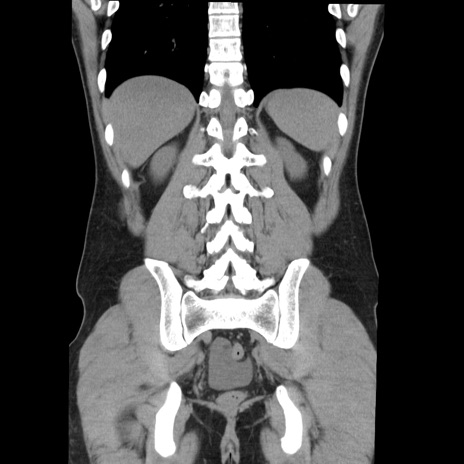

症例36(冠状断像)

【症例】20歳代 男性

【主訴】心窩部痛

【現病歴】今朝より上腹部痛あり。一旦軽快していたが再度出現したため救急要請。昨日夕に白身の魚を含む刺身を食べた。

【身体所見】BP 136/89mmHg、HR 74/min、BT 37.0℃、腹部:膨満、軟、心窩部に圧痛あり。反跳痛なし、筋性防御なし、腸雑音やや亢進あり。

【データ】WBC 17700、CRP 0.48

横断像